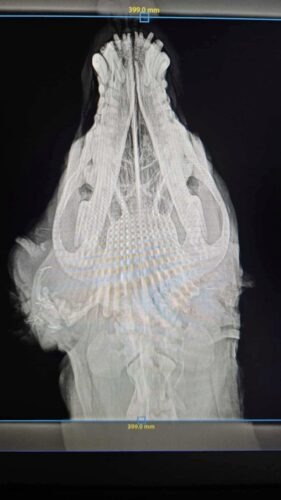

4 octobre 2025 : En début de semaine, on a emmené Ixia à la clinique parce que ça sentait très mauvais et ce n’était pas joli. Elle a été anesthésiée, ils ont nettoyé. Le canal auriculaire était d’aspect anormal et une biopsie a été faite, en attente de résultats. Des radiographies de la face ont été faites et ont été envoyées à des radiologues. Ils disent que les radiographies mettent en évidence une minéralisation du conduit auditif (plus probablement secondaire à son otite chronique). Elle a été mise sous convenia et on va voir comment ça évolue. Si ça ne va pas mieux il faudra probablement prévoir une ablation du conduit auditif. Elle est actuellement sous convenia + meloxicam pour gérer le côté infection et confort.